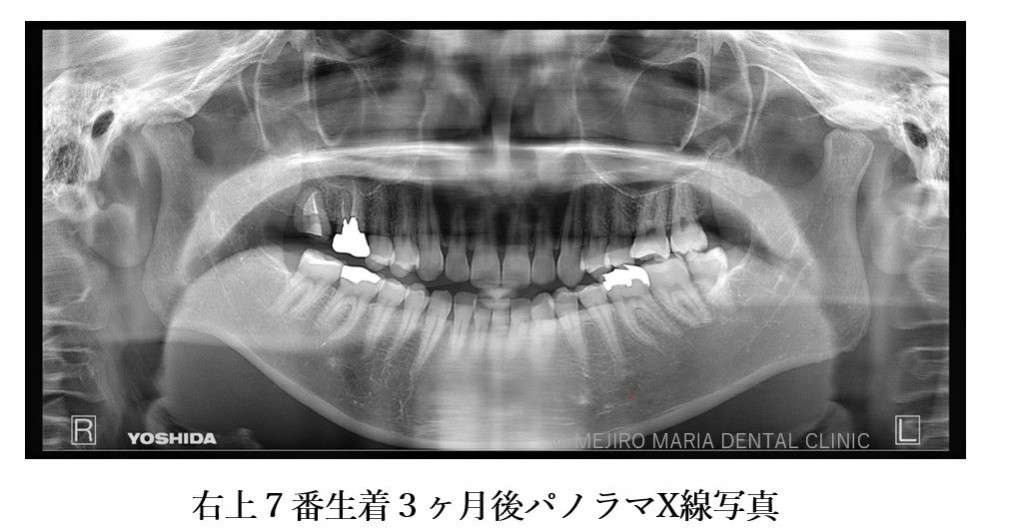

精密根管治療終了後3ヶ月で、術前に確認できた病変の縮小は顕著に確認でき、予後経過は良好と判断します。今後、最終補綴処置に移行し経過観察を行っていきます。

手術後、2週間で移植歯の生着を確認し、通法通りの精密根管治療を施したことで、根尖周囲組織に確認できた病変も3ヶ月後の経過観察では縮小を確認しました。